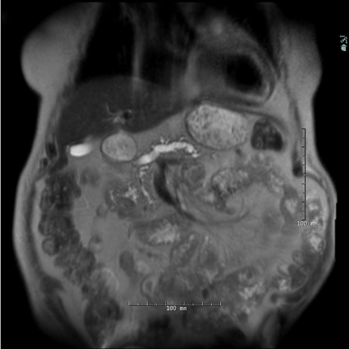

On examination, she is tender in the epigastric area and appears in mild distress. Labs demonstrate a normal serum lipase and mild elevation of alkaline phosphate (150 U/L). Computed tomography (CT) abdomen showed pancreatic parenchymal calcifications in the head and uncinate process. The pancreatic duct in the body and tail of pancreas was dilated to 12mm and intraductal calcifications were noted in the region of pancreatic head. MRI/MRCP confirmed dilatation of the main pancreatic duct dilation to 12 mm and a 10mm pancreatic duct calculus in the pancreatic head and chronic pancreatic volume loss.

MRI noting pancreas calculus with pancreas ductal dilation.

Image from the library of Rush University Medical Center.